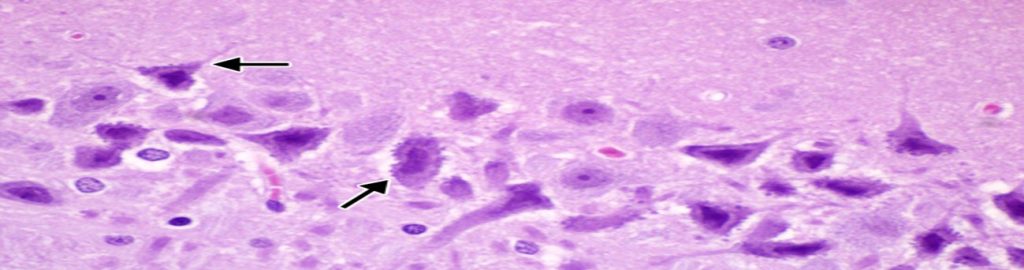

Glomus “The Glomus becomes paralyzed when blood clots obstruct the blood vessels. If this condition persists, the person is going to die. This new natural medicine treatment: GRF Medicine Restores your cell vitality and improves the quality of life. The usual wear and tear of our primary organs (kidney, stomach, liver, lung, heart). During the average lifetime of seven decades, our body grows old, and the average life of 80 to 85% of capillaries is damaged. We have 40 billion capillaries throughout our body (100,000 miles). “Glomus is the gateway to the blood, oxygen, nutrients and waste/sludge removal. Glomus is the bodies emergency response system that is triggered during life threatening incidents. “Glomus is the gateway to our body’s system of supplying blood, oxygen, and nutrients.

“Glomus must be attached to each capillary”.

Blood from the heart circulates in the order of the aorta, arteries, veins and capillaries.

When this natural circulatory system has problems, the blood stops and loses its place to go any further. Finally, people will die. A pale complexion when shocked and frightened causes a rapid contraction of the capillaries. This is because the blood is temporarily blocked.

The capillaries are said to be about 1/7 of the hair. When blood passes through the capillaries

Red blood cells, white blood cells, platelets, and other types of ingredient’s flow in a row single file. At this time, impurities in the blood (pigment, uric acid, thrombus & blood) cannot flow and capillaries If the tube is blocked, the glomus will become functionally disrupted within a few weeks. Cell tissues under these capillaries are more likely to stop nutrient supply and the problem is that hemoglobin in the red blood cells cannot supply oxygen, so the cells cause complications in proper functioning of body immune systems, leading to serious diseases including cancer.